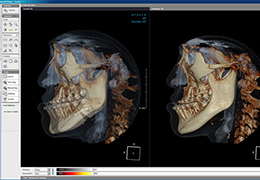

ANYTHINK 经导管主动脉瓣膜置换术分析系统